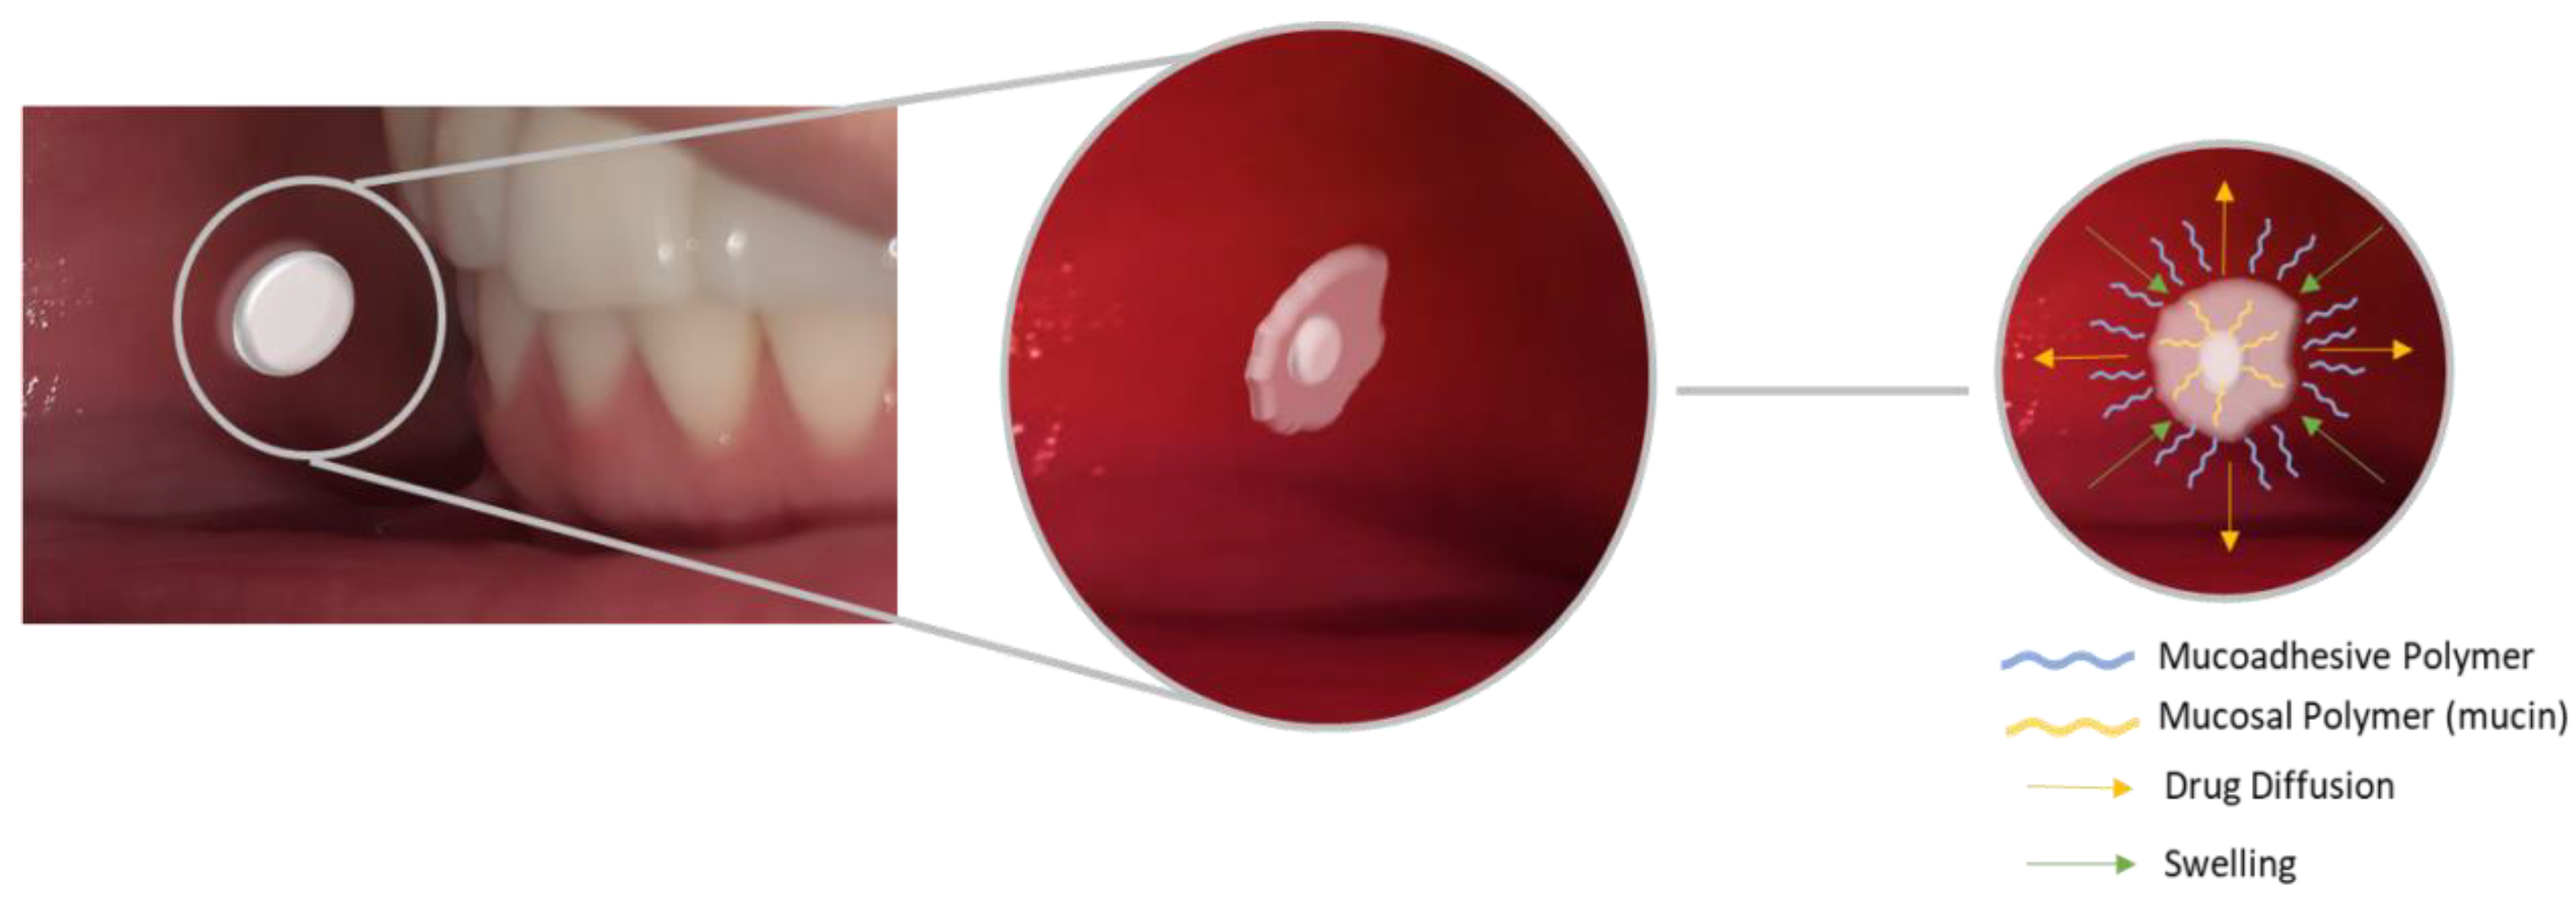

2.2. Mucoadhesive Biomaterials

2.2.2. Mucoadhesive Films and Gels